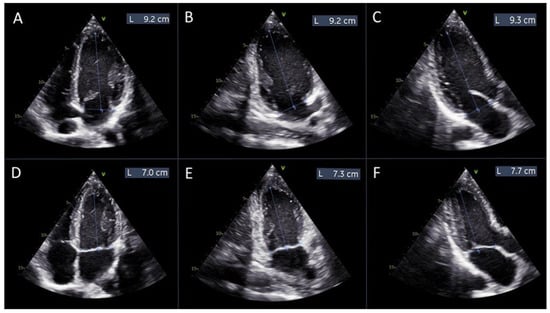

where L1d, L2d, and L3d are the distances from the mitral annulus plane to the apex of the left ventricle in diastole, measured in the 4-chamber, 2-chamber, and 3-chamber views, respectively (Figure 2A–C).

L1s, L2s, and L3s are the distances from the mitral annulus plane to the apex of the left ventricle in systole, measured in the same views (Figure 2D–F).

Figure 2. Measurements of left ventricular length for manual global longitudinal strain calculation. Panels (AC) display the measurements of the left ventricular length obtained from the apical 4-chamber, 2-chamber, and 3-chamber views, respectively, at diastole. Panels (DF) show the corresponding measurements from the same apical views at systole.